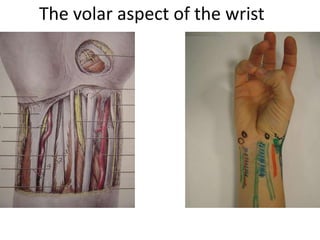

- Naming the bones, joints, tendons, nerves and skin landmarks of the hand and wrist.

- It describes flexor tendon zones, extensor compartments, and pulley system anatomy.